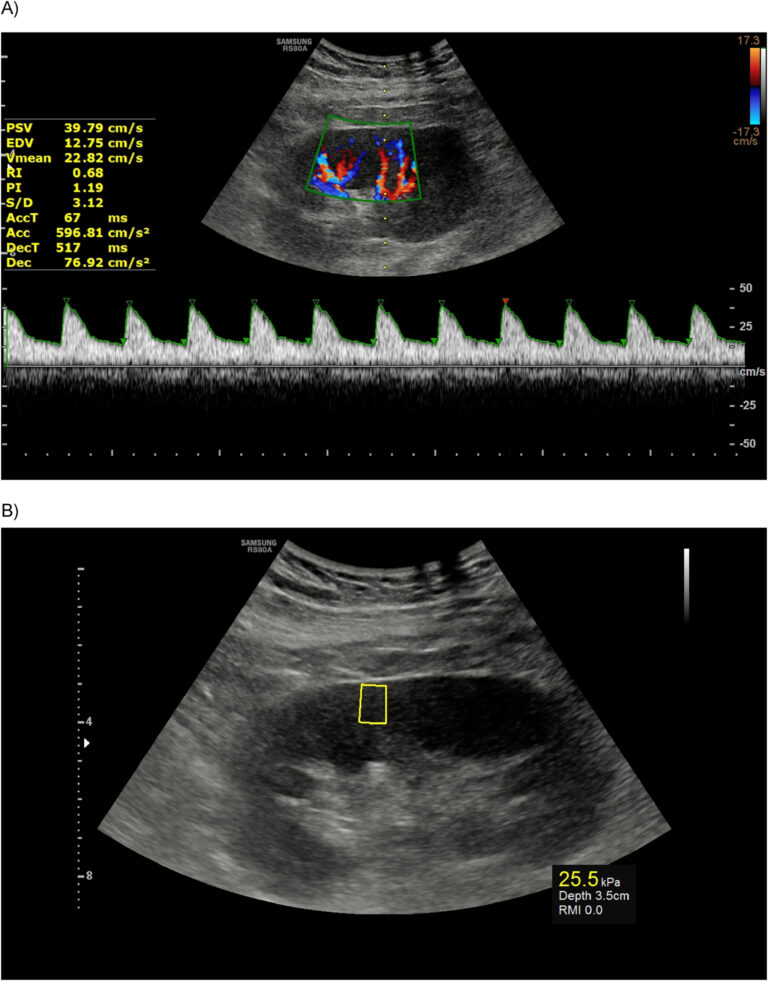

To develop and externally validate ultrasound nomograms combining BI-RADS features and quantitative morphometric characteristics, and to compare their performance with expert radiologists and large language models in biopsy recommendation and malignancy prediction for breast lesions…